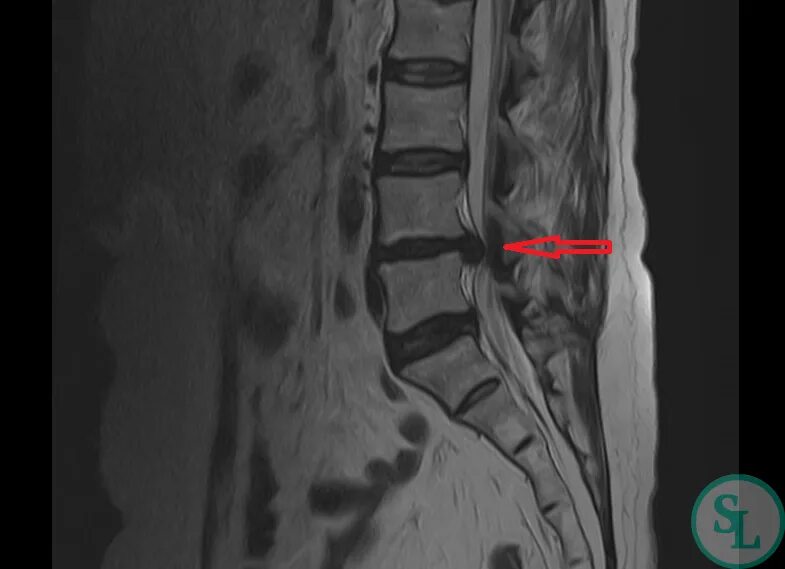

Протрузии межпозвонковых дисков l4 s1